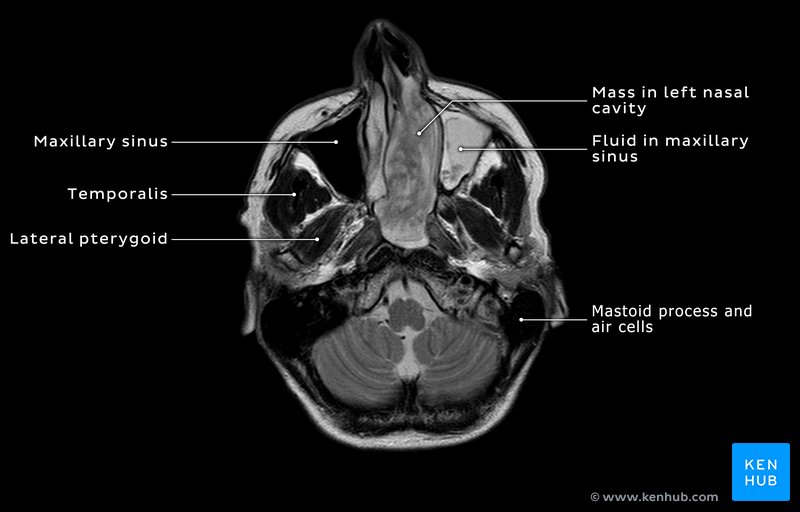

There was also hyperostosis (increased density) of the sphenoid and maxillary sinus walls (Figures 2–3). An MRI was done to provide a better estimation of the extent of the soft tissue mass than obtainable from CT mages. The MRI images showed that the mass occupied the entire left nasal cavity, extending into the choanae to completely fill the nasopharynx (Figures 4&5).

The mass measured 78×28×51mm (AP×ML× SI). The mass also filled the left anterior and posterior ethmoid air cells, obliterating all bony septations (Figure 3). The left maxillary sinus and frontal sinus were filled with mucus secretions secondary to the obstruction caused by the tumor (Figures 4&5).

Importance of MRI and CT scans in tumor diagnosis

MRI provides much better soft tissue resolution than CT, whereas CT provides better bony resolution. Thus, the hyperostosis of the bony walls of the nasal cavity is clearly seen on the coronal and axial CT images, but not on the comparable MRI images (Figures 2-5). However, the coronal and axial T2 weighted MRI images (fluid appears bright) show that the mass within the maxillary sinus is not the same as the mass within the nasal cavity and nasopharynx.

In the MRI images the maxillary sinus mass has a higher intensity than that of the tumor and therefore, as noted in the text, is not part of the tumor mass but rather is mucous that has been secreted in response to the tumor. This difference was not discernible in the CT images and this information informed the surgeons that they did not need to involve the maxillary sinus in their surgical extirpation but rather they just needed to drain the sinus.